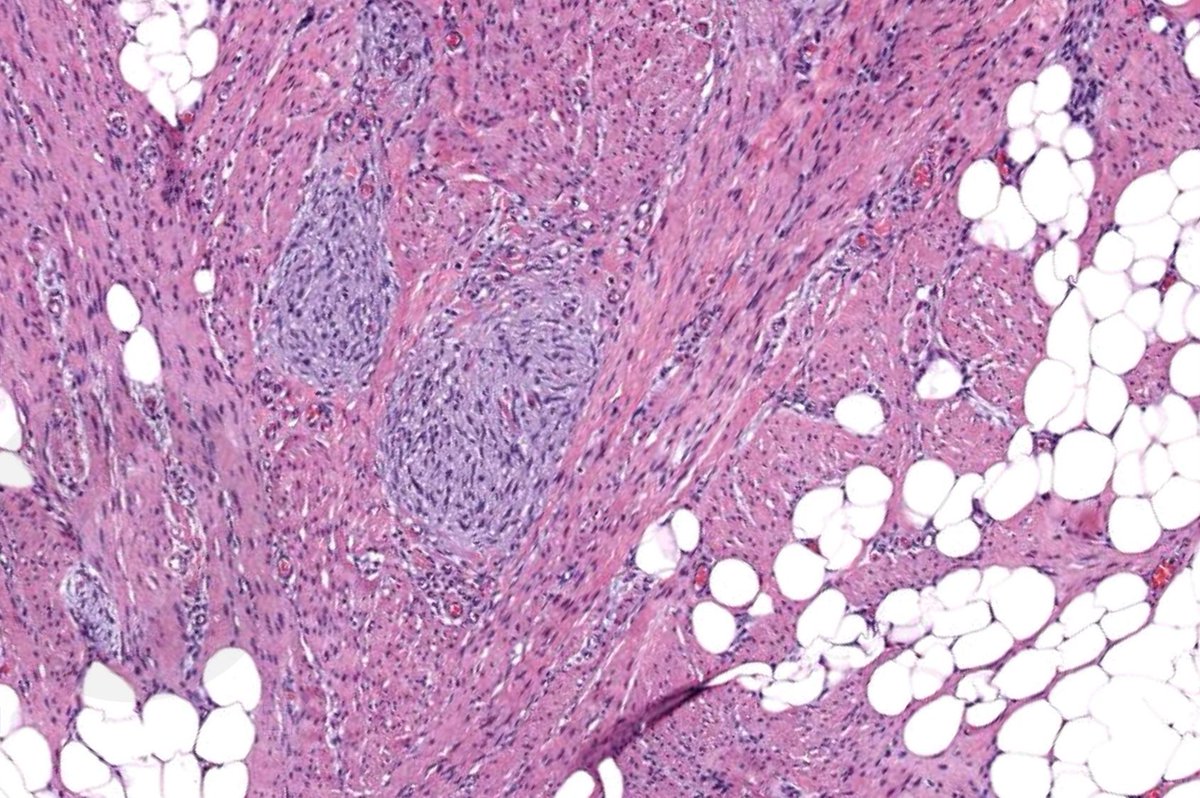

A slow-growing soft tissue mass in a child; histology shows distinctive findings and MUC4 IHC is +. Likely diagnosis? diagnostic gene fusion? #pedipath #softtissuepath #molecpath 🤔🔬🧬

7

35

102